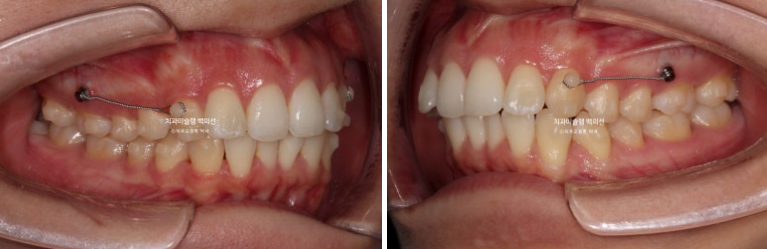

23.10

어금니 후방이동에 필요한 교정용 나사를 심고 진행합니다.

24.02

앞니와 송곳니가 뒤로 가야하는 단계에서는 이런 장치도 붙입니다.

현재는 여러가지 이유로 환자분이 뺐다 꼈따 하는 고무줄 처방이 같이 나갔겠지만 저 당시에는 고무줄 처방 없이 저렇게 후방이동을 시켰습니다.